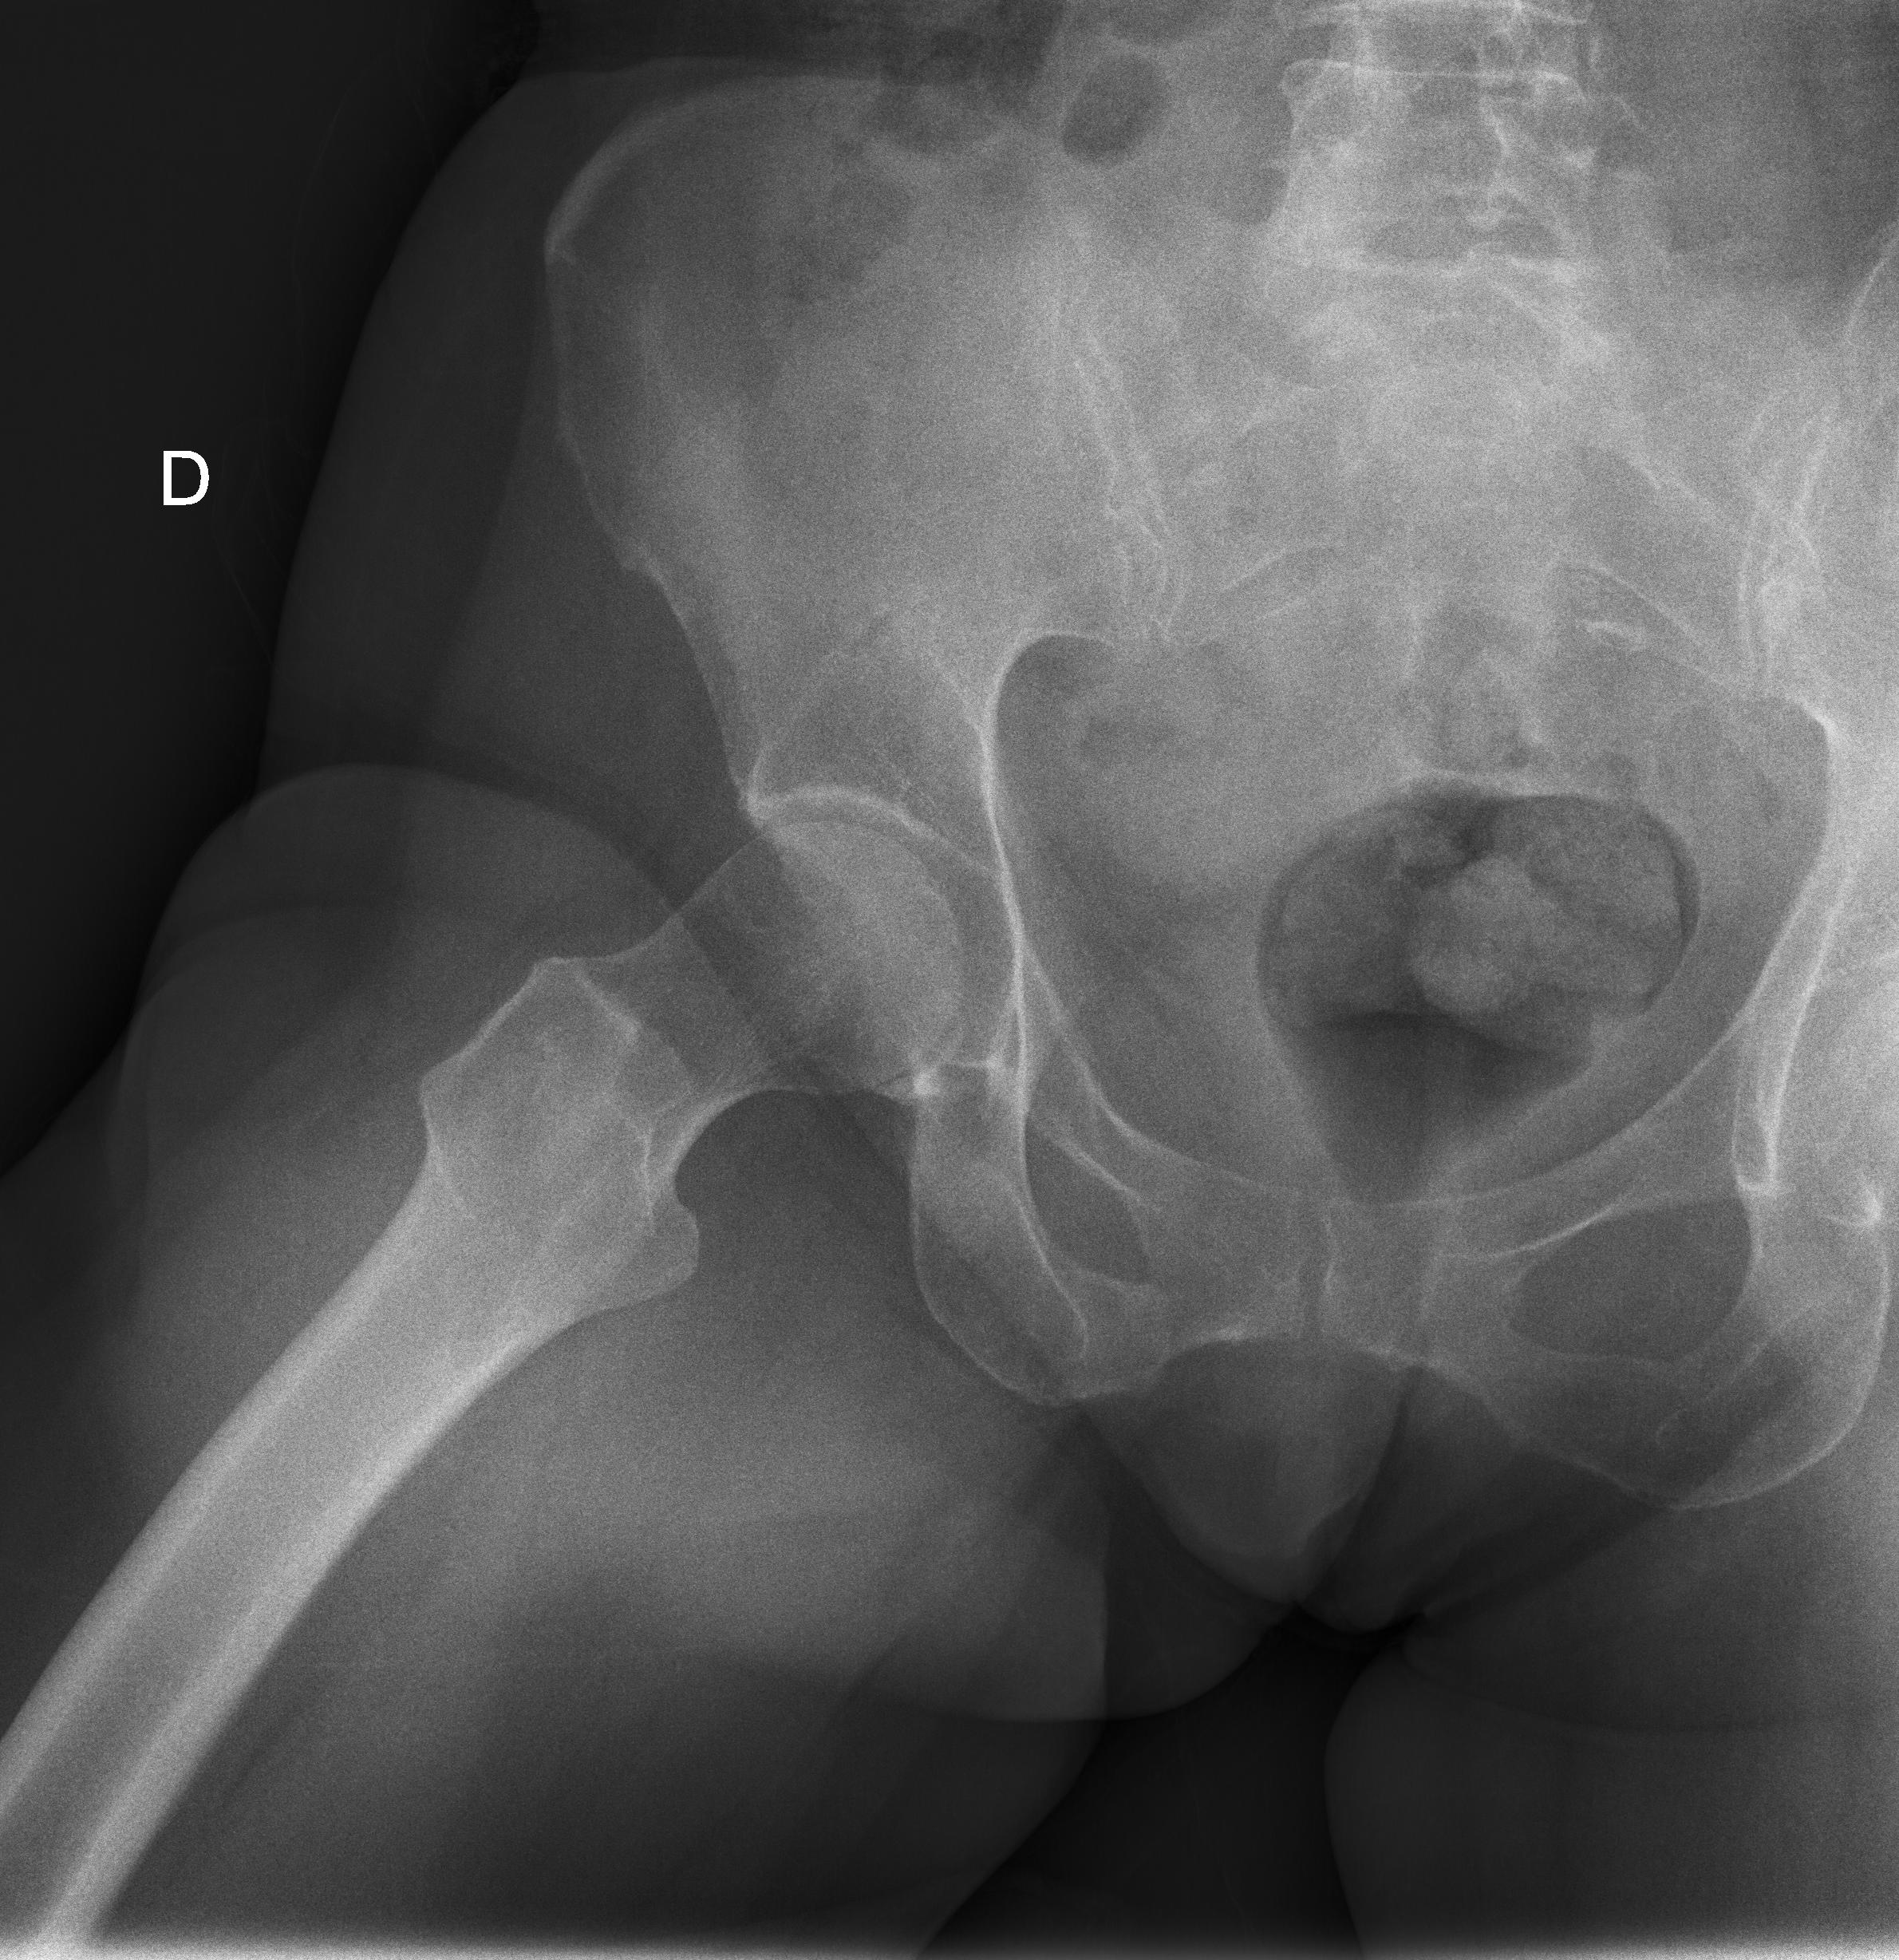

1 Cadera(s)